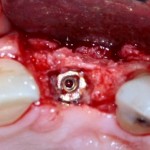

Например, в следующей ситуации:

Оставить так, как есть — это значит, сильно рисковать имплантом и объемом альвеолярного гребня — фактически, большая часть импланта пятого зуба «висит в воздухе». Поэтому получившуюся костную полость мы заполняем аутокостной стружкой в смеси с Bioss и закрываем коллагеновой мембраной BioGide:

При необходимости, мембрану можно фиксировать пинами.

Через три месяца результат:

можно ставить формирователи и заканчивать лечение:

В указанном выше случае использование костных блоков просто невозможно.